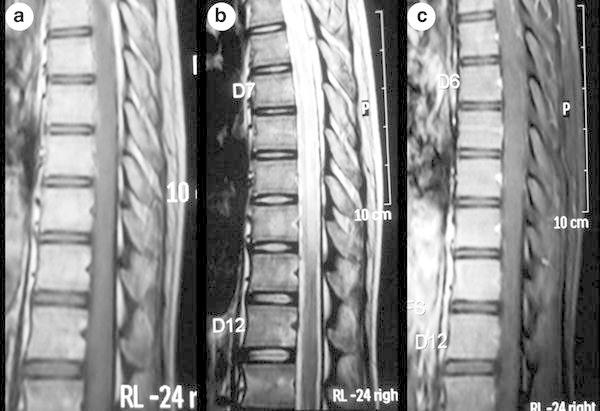

The magnetic resonance imaging (MRI) of thoracic spine showed contiguous long segment intramedullary lesion, which was isointense on T1-weighted and hyperintense on T2-weighted images extending from thoracic vertebral level T2 to T10. There was no cord expansion or contrast enhancement (Figs. 2a–c, 3a–d). The MRI features were suggestive of longitudinally extensive transverse myelitis (LETM). The MRI of brain showed no new changes.

Fig. 2.

Magnetic resonance imaging (MRI) of thoracic spine (sagittal section) showing contiguous long segment intramedullary lesion which is isointense on T1-weighted (a) and hyperintense on T2-weighted (b) images extending from thoracic vertebral level T2 to T10. There is no cord expansion or contrast enhancement (c)